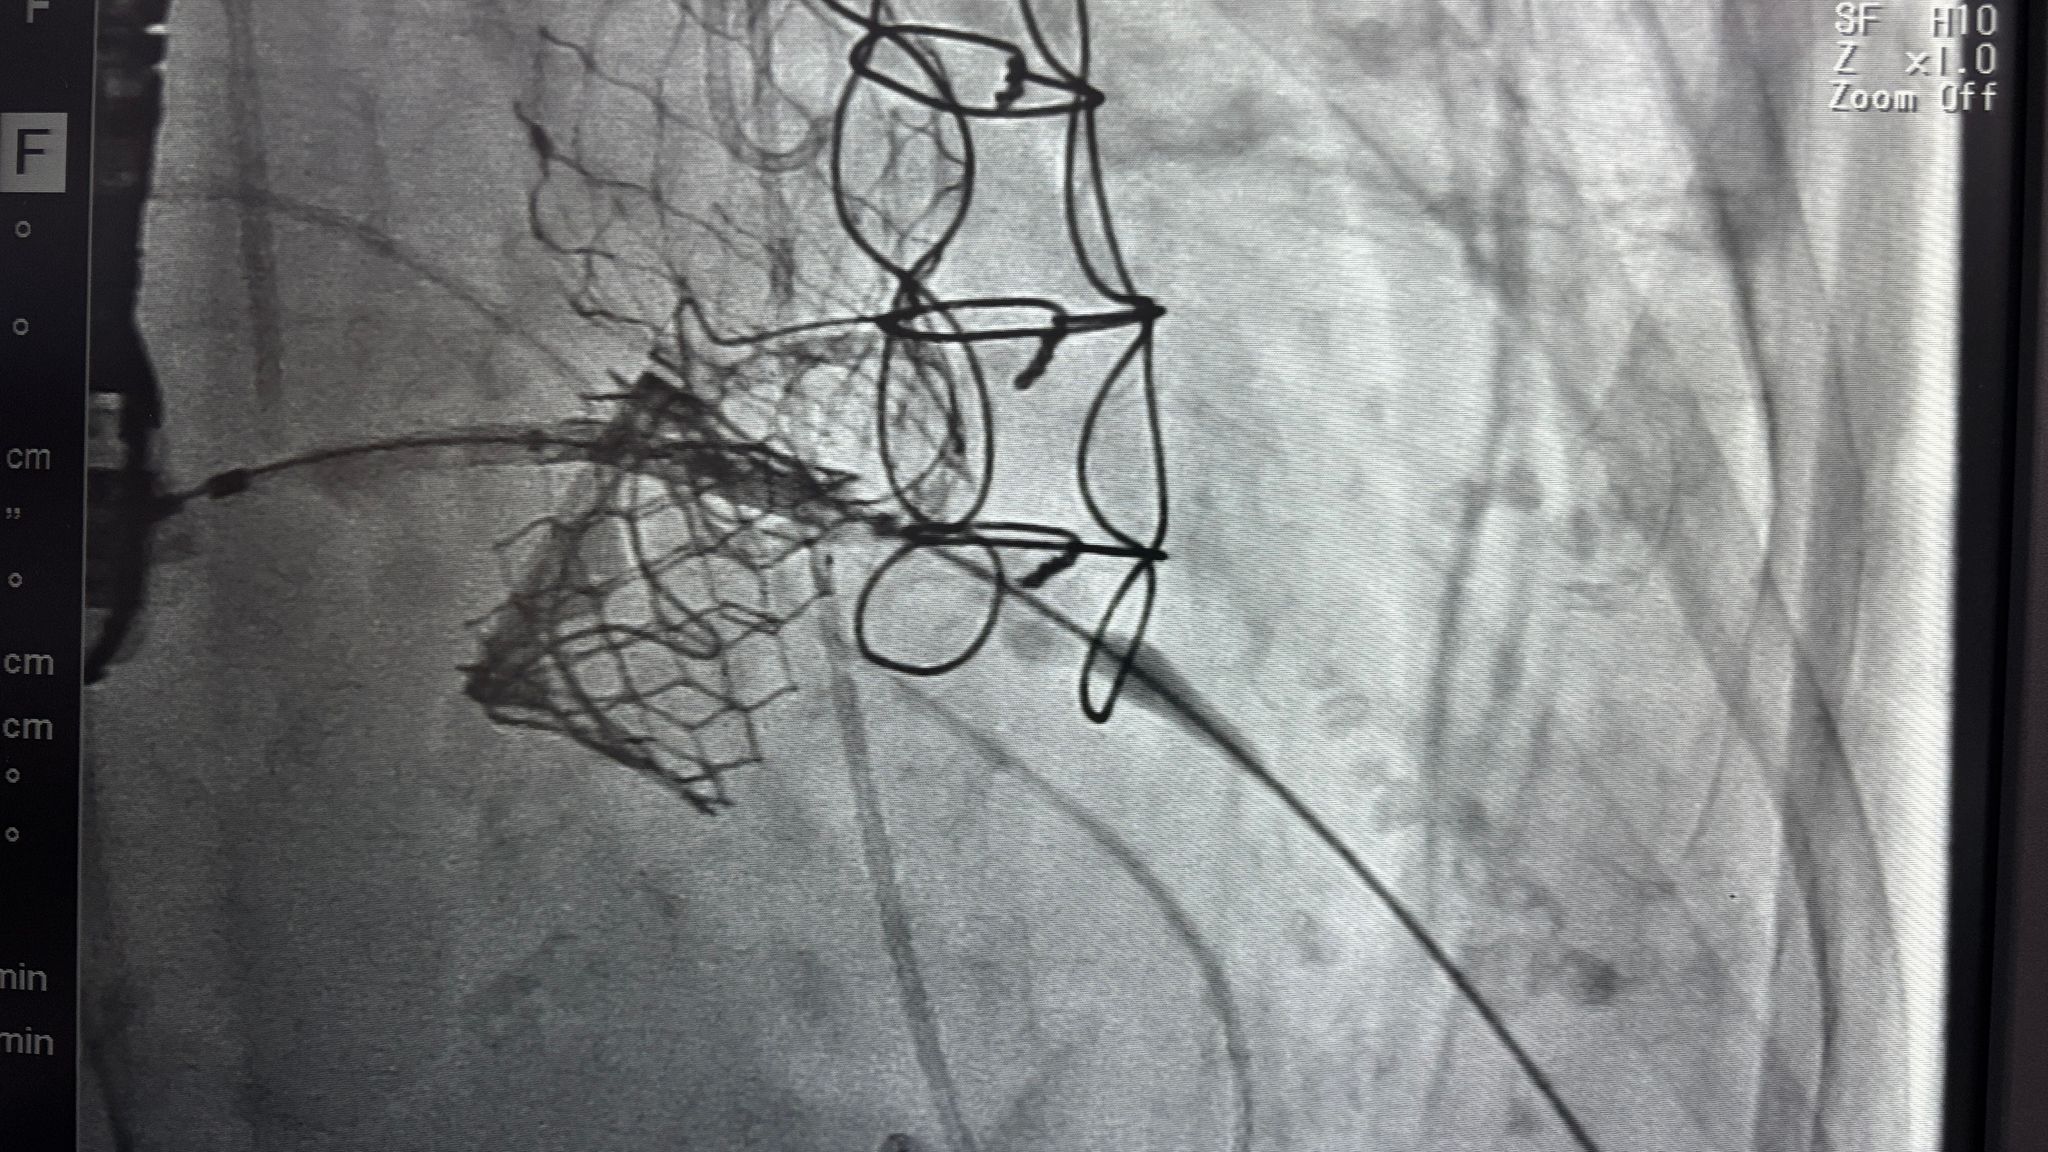

放完Mitral的時候,血氧很差,正當大家一臉矇的時候,只有我快速反應到,可能是ASD導致的shunting的關係

我在嘟囔著的時候,被宋大師聽到了,趕快請麻醉科進行確認,果不其然是Right to left shunt

比大家早一步反應,覺得還是挺有成就感的!善哉善哉~